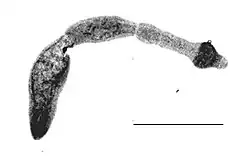

| Echinococcus multilocularis isolated from a fox | |

Morphology

The adult parasite is a small tapeworm that is 3-6 mm long, and lives in the small intestine of canines. The segmented worm contains a scolex with suckers and hooks that enable attachment to the mucosal wall, since tapeworms do not have a digestive tract. A short neck connects the head to three proglottids, the body segment of the worm which contains the eggs to be excreted in the feces.[6]